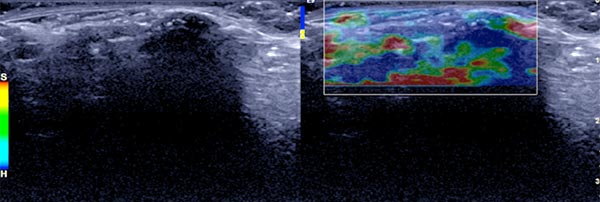

In der Sonographie (B-Bild) findet sich durch den hohen Bindegewebsanteil an der Oberfläche des Nävus direkt eine totale Schallreflexion mit einem ausgeprägten Schallschatten. Die Läsion selbst ist nicht darstellbar.

In der farbkodierten Duplexsonographie (FKDS) zeigt sich ebenfalls die totale Schallreflexion. Auch bei sehr empfindlicher Einstellung für Blutfluss (6 cm/s) keinerlei Perfusion feststellbar.

In der Ultraschall-Elastographie kodiert die Läsion entsprechend der hohen Gewebehärte weitgehend hart.